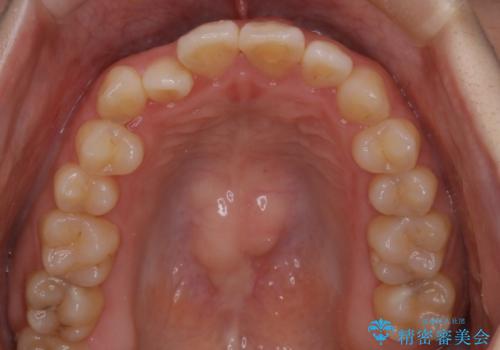

【インビザライン】前歯のがたつきを目立たない装置で治療

- 前歯の叢生を主訴に来院されました。目立たない装置を希望されたためインビザラインで治療を行いました。

IPRと拡大をし、叢生を治しました。右上2番は反対咬合でしたが短期間できれいに治りました。